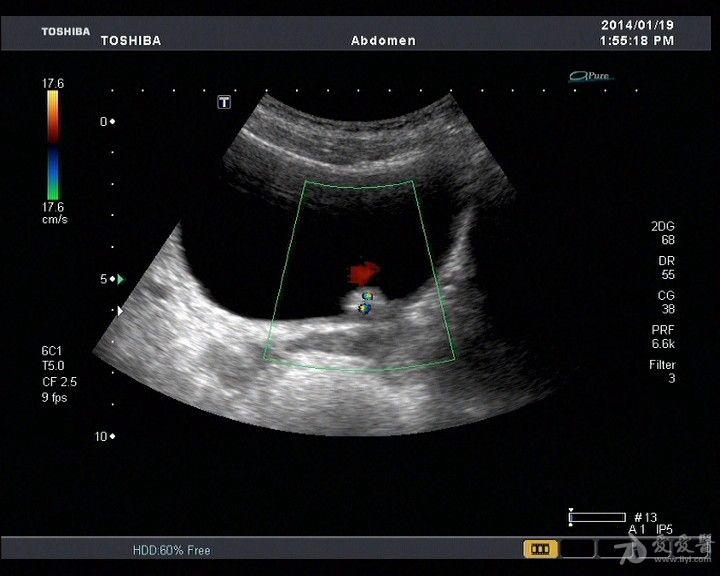

早期膀胱癌的彩超图

典型膀胱占位两例!(膀胱癌)